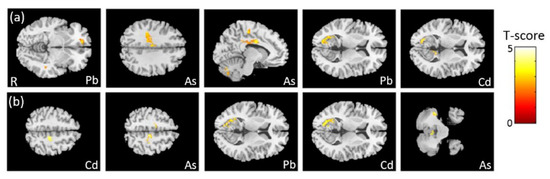

3.4. The Association between Heavy Metals and VBM

3.6. The Association between PFCs and GQI